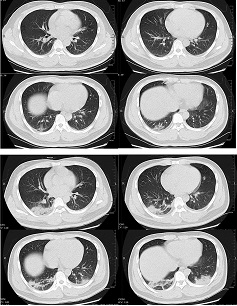

Transverse CT scans from a 32-year-old man, showing ground-glass opacity and consolidation of lower lobe of right lung near the pleura on day 1 after symptom onset (top panel), and bilateral ground-glass opacity and consolidation on day 7 after symptom onset

Xu XW et al. BMJ. 2020;368:m606